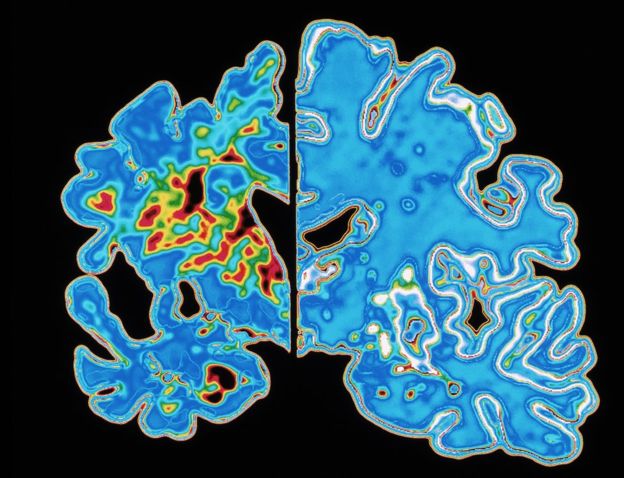

La demencia fue descrita por primera vez por el médico alemán Alois Alzheimer en 1906 tras realizar una autopsia a una mujer que había sufrido pérdida profunda de memoria.

Lo que encontró fue un cerebro muy reducido y anomalías en y alrededor de las células nerviosas.

Algunos signos se pueden encontrar a veces en el cerebro después de la muerte.